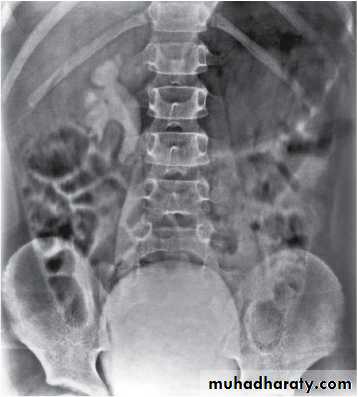

The degree of reflux is graded I–V.Grading is based on the appearance of contrast agent in the collecting system during voiding cystourethrography (VCUG(.

The VCUG:

the definitive examination

to diagnose and grade reflux and establish reversible causes

must include a voiding phase:

in some cases, reflux may be seen only during the elevated intravesical pressures associated with micturition.

in visualizing the urethra, may allow the diagnosis of outflow obstruction to be made (e.g., posterior urethral valves).

MCUG